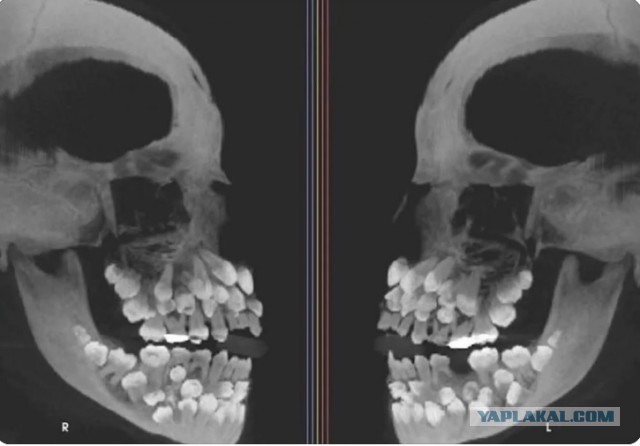

Рентгеновский снимок пациента с гипердонтией (состояние, когда зубов больше, чем обычно). Обычно взрослые имеют 32 зуба. А у этого человека 81.

Такому палец в рот не суй!

Зубастик